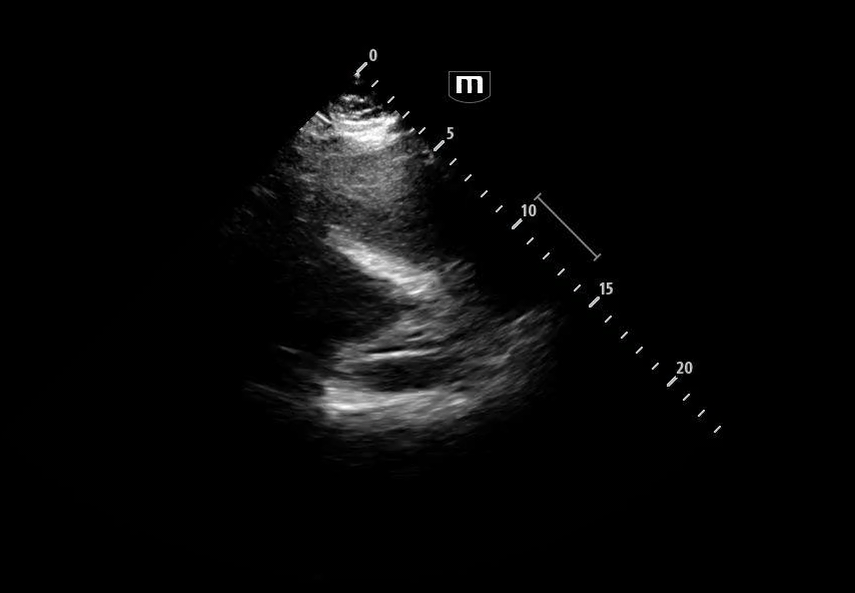

Image 4 instead reveals cardiac activity visualized to the right of the sternal border, suggesting mediastinal shift.

Image 5 shows a subxiphoid cardiac view

Image 6 demonstrates a plethoric inferior vena cava (IVC), concerning for elevated intrathoracic pressure and impaired venous return.